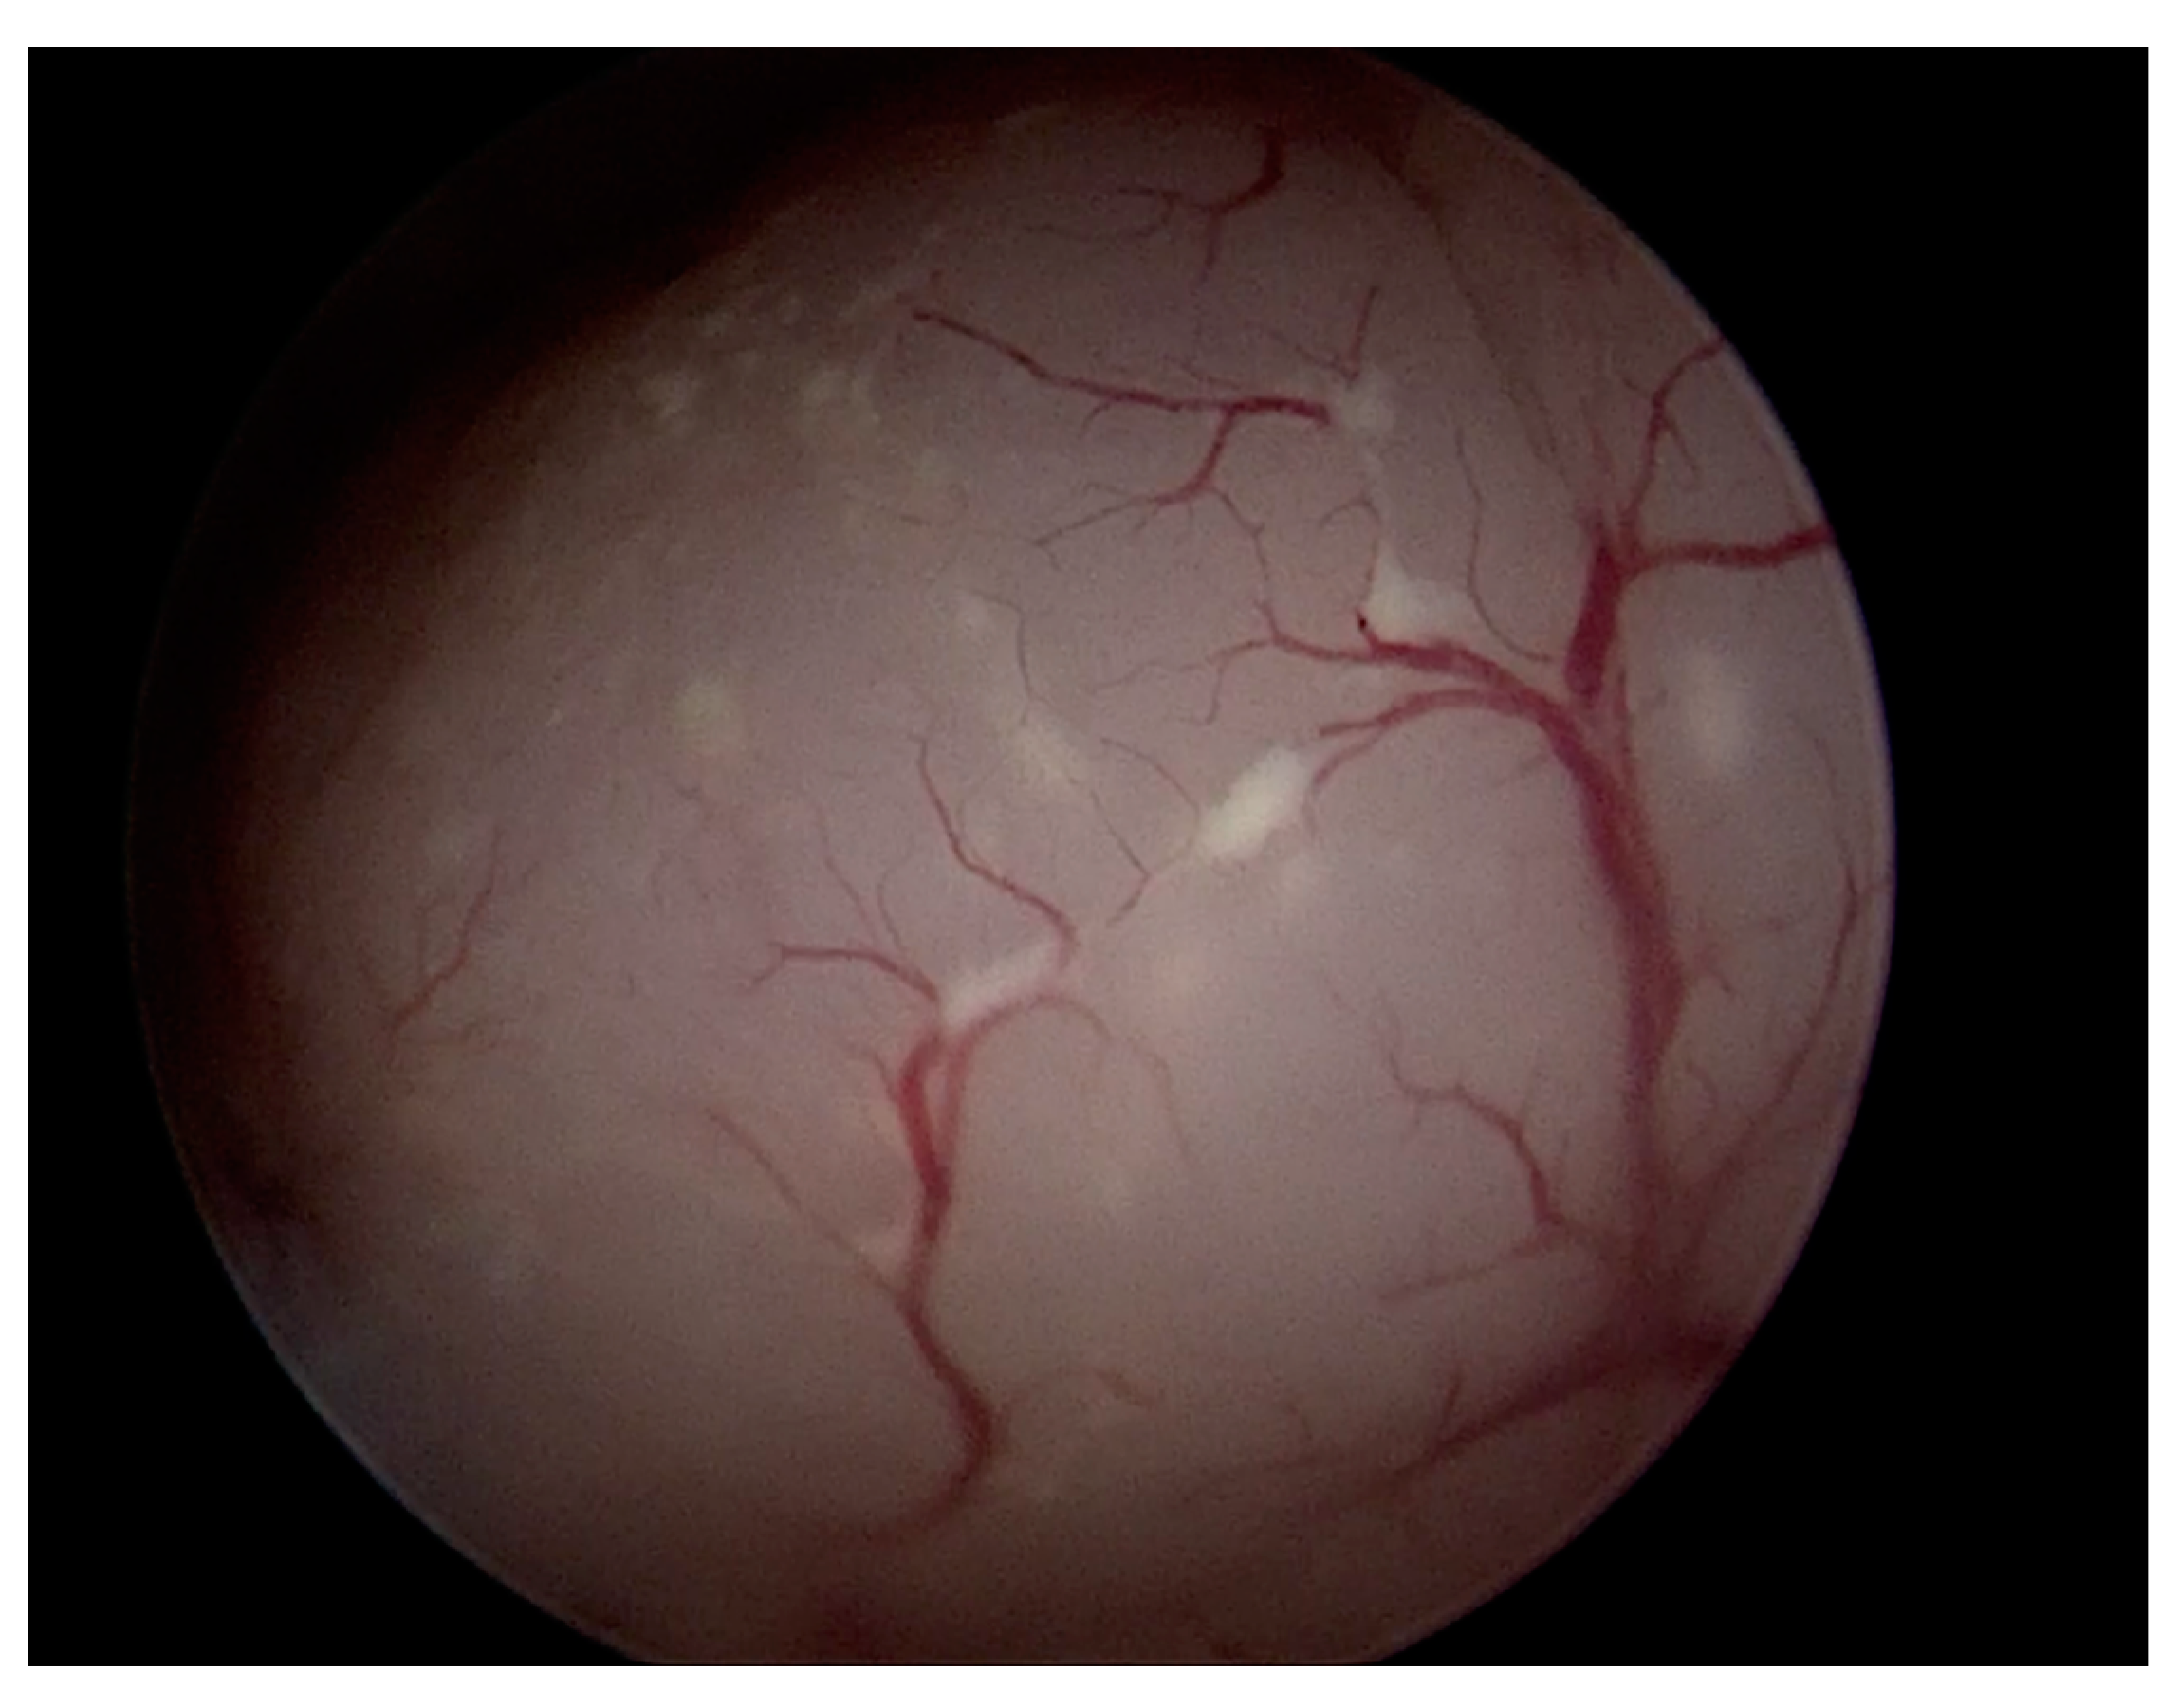

- A hysteroscopy was performed in an outpatient setting by two highly trained expert operators (A.F. and G.P.) with an endometrial biopsy. All the procedures included vaginoscopy, distension of the uterine cavity with normal saline, diagnostic evaluation of the cervical canal and uterine cavity with visualization of tubal ostia, and targeted biopsy on any suspicious area of the endometrium using a BETTOCCHI® Hysteroscope equipped with bipolar electrode systems [9]. Diagnosis of AEH was made on endometrial specimens according to WHO 2014 criteria [1].

- The hysteroscopic reports about the appearance of the lesion (protruding into the uterine cavity vs. superficial anomaly of the endometrium), presence of necrosis or atypical vascular pattern, subjective assessment indicative of carcinoma by the operator, and visualization of tubal ostia;

| Hysteroscopy features | Protruding intracavitary lesion (%) | 48 (60) |

| Necrosis (%) | 24 (31.6) | |

| Atypical vascularization (%) | 44 (58.7) | |

| Visualization of tubal ostia (%) | 80 (100) | |

| Subjective assessment suggesting cancer (%) | 43 (58.1) | |

| Protruding intracavitary lesion (%) | 21 (77.8) | 27 (50.9) | 0.029 |

| Necrosis (%) | 1 (4.2) | 23 (44.2) | 0.001 |

| Atypical vascularization (%) | 8 (33.3) | 36 (70.6) | 0.003 |

| Visualization of tubal ostia (%) | 27 (100) | 53 (100) | - |

| Subjective assessment suggesting cancer (%) | 3 (12.5) | 40 (80.0) | 0.001 |